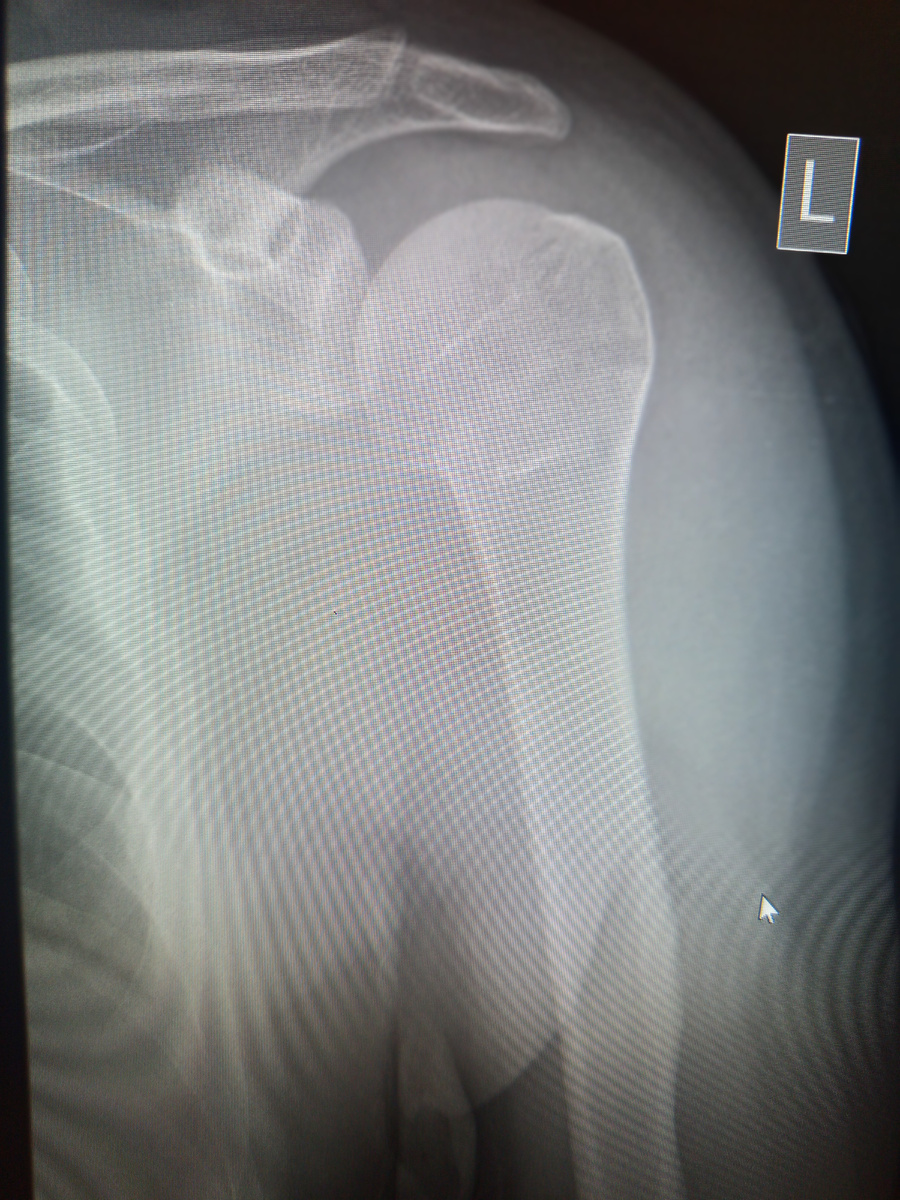

Пришел мужчина , 28 лет на снимок плечевого сустава.

Лина , видя , что он двигает рукой без ограничений , бросает мне:

–Одна проекция будет.

Пока пациенту накидывал футболку,снимок проявился:

–Лин , делай вторую проекцию, мне не "нравится "сустав.

Не нравится мы говорим , когда видим подозрение на перелом.

–Вставайте обратно, надо доснять, –командует Лина. –А вообще , что с вами случилось?

–Я с конч упал. Можно посмотреть потом снимок?

–А вы понимаете?

–Я мед закончил , хирург я.

–Идите , смотрите тогда ," коллега".

–А , ну , вижу , ничего , вроде нет.

Мы с Линой просто переглянулись. Хирург полостной может в травме ничего не понимать, это нормально.

–Идите , на контрольный снимок придете.

–На какой? Там же все нормально?

–Идите, сами узнаете.

Конечно на контроль он пришел, удивлялся , как это он врач не увидел перелом , а техники увидели сразу)

Пришлось его удивить , что мы анатомию костей и органов знаем , как Отче наш, и изначально мы все со средним , это потом решили идти в рентгенолаборанты, ибо не искали сложных путей))